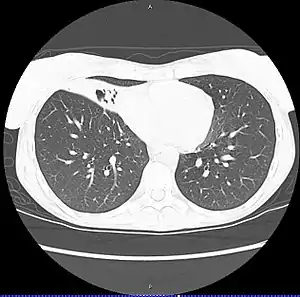

| CT scan of patient with right middle lobe aspiration and Mycobacterium avium infection consistent with Lady Windermere syndrome | |

MAC usually affects patients with abnormal lungs or bronchi. However, Jerome Reich and Richard Johnson describe a series of six patients with MAC infection of the right middle lobe or lingula who did not have any predisposing lung disorders.[18][19]

The right middle lobe and lingula of the lungs are served by bronchi that are oriented downward when a person is in the upright position. As a result, these areas of the lung may be more dependent upon vigorous voluntary expectoration (cough) for clearance of bacteria and secretions.

Since the six patients in their retrospective case series were older females, Reich and Johnson proposed that patients without a vigorous cough may develop right middle lobe or left lingular infection with MAC. They proposed this syndrome be named Lady Windermere syndrome, after the character Lady Windermere in Oscar Wilde's play Lady Windermere's Fan. However, little research has confirmed this speculative cause.[20]